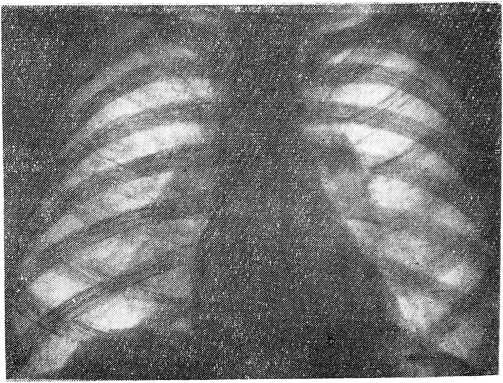

Сопоставляя в таблице 3 стандартные рентгенограммы с флюорограммами различных размеров одного и того же больного, мы идентичность снимков отмечали как «полное совпадение» в диагнозе (рис. 1). Флюорограммы же, не отражавшие в достаточной степени качественной характеристики процесса и затруднявшие качественную диагностику, мы обозначали термином «частичное расхождение» в диагнозе. Расхождение в диагнозе количественного и качественного характера мы отмечали как «несовпадение».

Рис. 1 а

Рис. 1 б

Только по одному случаю при определении диагноза инфильтративного и фиброзно-кавернозного туберкулеза легких на флюорограмме размером 7 X 7 см было отмечено «частичное расхождение» в диагнозе в сравнении с обычной рентгенограммой. В то же время по мелкокадровым флюорограммам при перечисленных формах туберкулеза легких получено: частичных расхождений — 2 при первичном комплексе, 4 — при инфильтративном туберкулезе легких, 4 — при фибрознокавернозном туберкулезе легких.